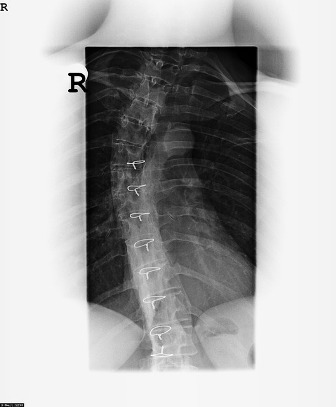

The chiropractor will appreciate having access to your x-rays simply to confirm the exact location of the problem. Additionally, any surgical procedures performed should be amply documented, preferably with a prognosis for results and a summary of results actually obtained, and also an exact summary of the medications prescribed, the frequency of injections, and the outlook for progression. Sadly, in younger patients progression is much more likely than in adult onset cases, yet each case revolves on its own facts and there is no guarantee of stemming the effects of scoliosis.